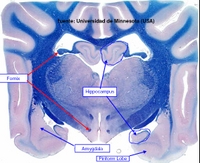

El Sistema Olfatorio y el Sistema Límbico.

El Sistema Olfatorio es el encargado de recoger las sensaciones del olfato. Las neuronas de primer orden o células receptoras son neuronas bipolares localizadas en el EPITELIO OLFATORIO. Los axones no mielinizados de estas neuronas se recogen en manojos que colectivamente forman el NERVIO OLFATORIO. Este nervio penetra la LÁMINA CRIBIFORME del hueso etmoides para entrar en el BULBO OLFATORIO, donde se encuentran las células mitrales (neuronas de segundo orden) las cuales envían sus axones formando el TRACTO OLFATORIO o ESTRIA. El bulbo olfatorio consta de varias capas: una glomerulas (donde las fibras de los nervios olfatorios sinapsan con las dendritas de las células mitrales), una capa de células mitrales y una capa de células granulares.

El tracto olfatorio termina por una bifurcación en la ESTRIA OLFATORIA MEDIAL y LATERAL, las cuales proyectan respectivamente al AREA SEPTAL (responsable de los reflejos olfatoviscerales) y a la CORTEZA PIRIFORME (responsable de la sensación consciente de la olfación).

El RINENCÉFALO está formado por el lóbulo piriforme y por el bulbo olfatorio.

El Sistema Límbico comprende a estructuras de la corteza cerebral que bordean el tronco encefálico, junto a ciertos componentes del hipotálamo, tálamo y epitálamo, y está relacionado con la percepción de las emociones de importancia para la supervivencia del animal, como la defensa, alimentación, escape, etc.. y emociones asociadas con la supervivencia de la especie, tales como la defensa territorial, cortejo, apareamiento, etc.., estando además relacionado con procesos relativos al aprendizaje y memoria.

HIPOCAMPO: Es una estructura de la corteza cerebral con 3 capas de células, llamada ARQUEOCORTEX, de importancia en aprendizaje asociativo y memoria (particularmente memoria de corto tiempo). Tanto pacientes amnésicos como animales con daños en hipocampo exhiben problemas tiempo-dependientes en tareas de comportamiento generalmente descritas como asociativas o relacionadas por naturaleza. Este área del cerebro tiene un bajo umbral de ataques o convulsiones.

AMIGDALA: Es una región altamente diferenciada cerca del polo temporal de los hemisferios cerebrales de los mamíferos. Es un núcleo basal que está implicado en la emoción, memoria, comportamiento social, comportamiento reproductor, miedo y agresión, y modulación de sistemas autonómicos y neuroendocrinos. Muchos de sus efectos son opuestos a los del septum. Lesiones de la amígdala pueden suponer comportamiento dócil, mientras que su estimulación produce comportamiento agresivo.

AREA SEPTAL o SEPTUM: este área de la corteza cerebral está envuelta en varios procesos fisiológicos y de comportamiento, tales como emociones, alivio del miedo, comportamiento dócil y estrés, además de en procesos de regulación autonómica ( ingesta de comida o agua, hibernación, etc..). Su estimulación lleva a un comportamiento dócil, y puede suprimir muchas respuestas autonómicas.

LÓBULO PIRIFORME del RINENCÉFALO. Entra dentro del sistema límbico ya que tiene funciones afectivas junto a otras estructuras límbicas tales como impulsos o ciertas conductas de comportamiento.